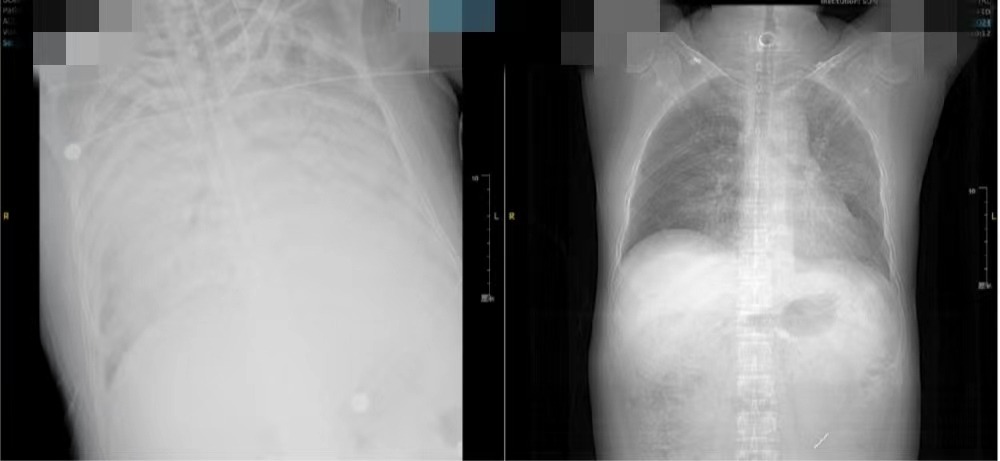

曹先生去附近一家医院就诊,一拍胸片才发现,此时他的双肺已经出现了大面积的“白肺”,随即住进了当地ICU,并接受了气管插管及呼吸机辅助呼吸治疗。因一度出现极度缺氧,病情严重的他被紧急转送至中山大学孙逸仙纪念医院急诊EICU接受进一步治疗。

治疗前“大白肺”(左)和治疗后(右)对比